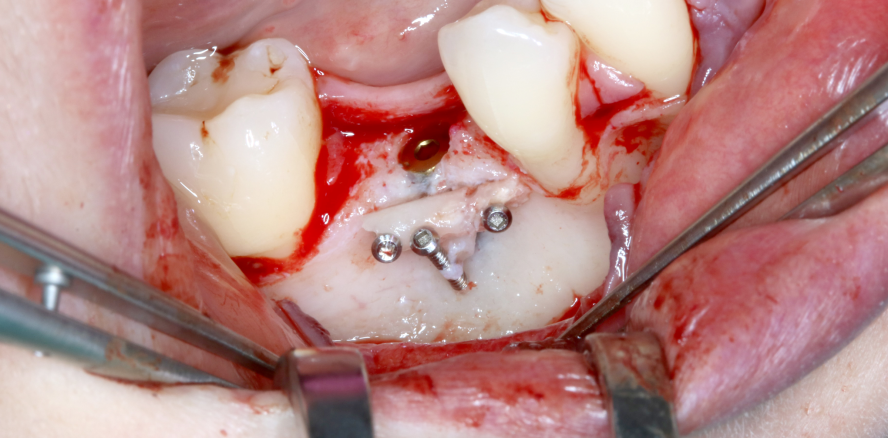

Bei jedem chirurgischen Eingriff an knöchernen Strukturen, wie beispielsweise der intraoralen Transplantation von Knochenblöcken, besteht das...

Bei jedem chirurgischen Eingriff an knöchernen Strukturen, wie beispielsweise der intraoralen...